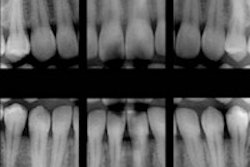

For example, before you acquire digital radiography, you need to have the computer infrastructure in place. If your staff will be using the technology, what training will they need to ensure they have the skills to use the technology efficiently?